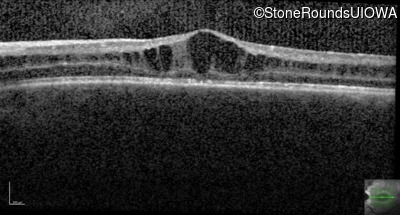

Optical Coherence Tomography - Left - 20/50 -2

Exemplar / OCT Stack

OCT Stack